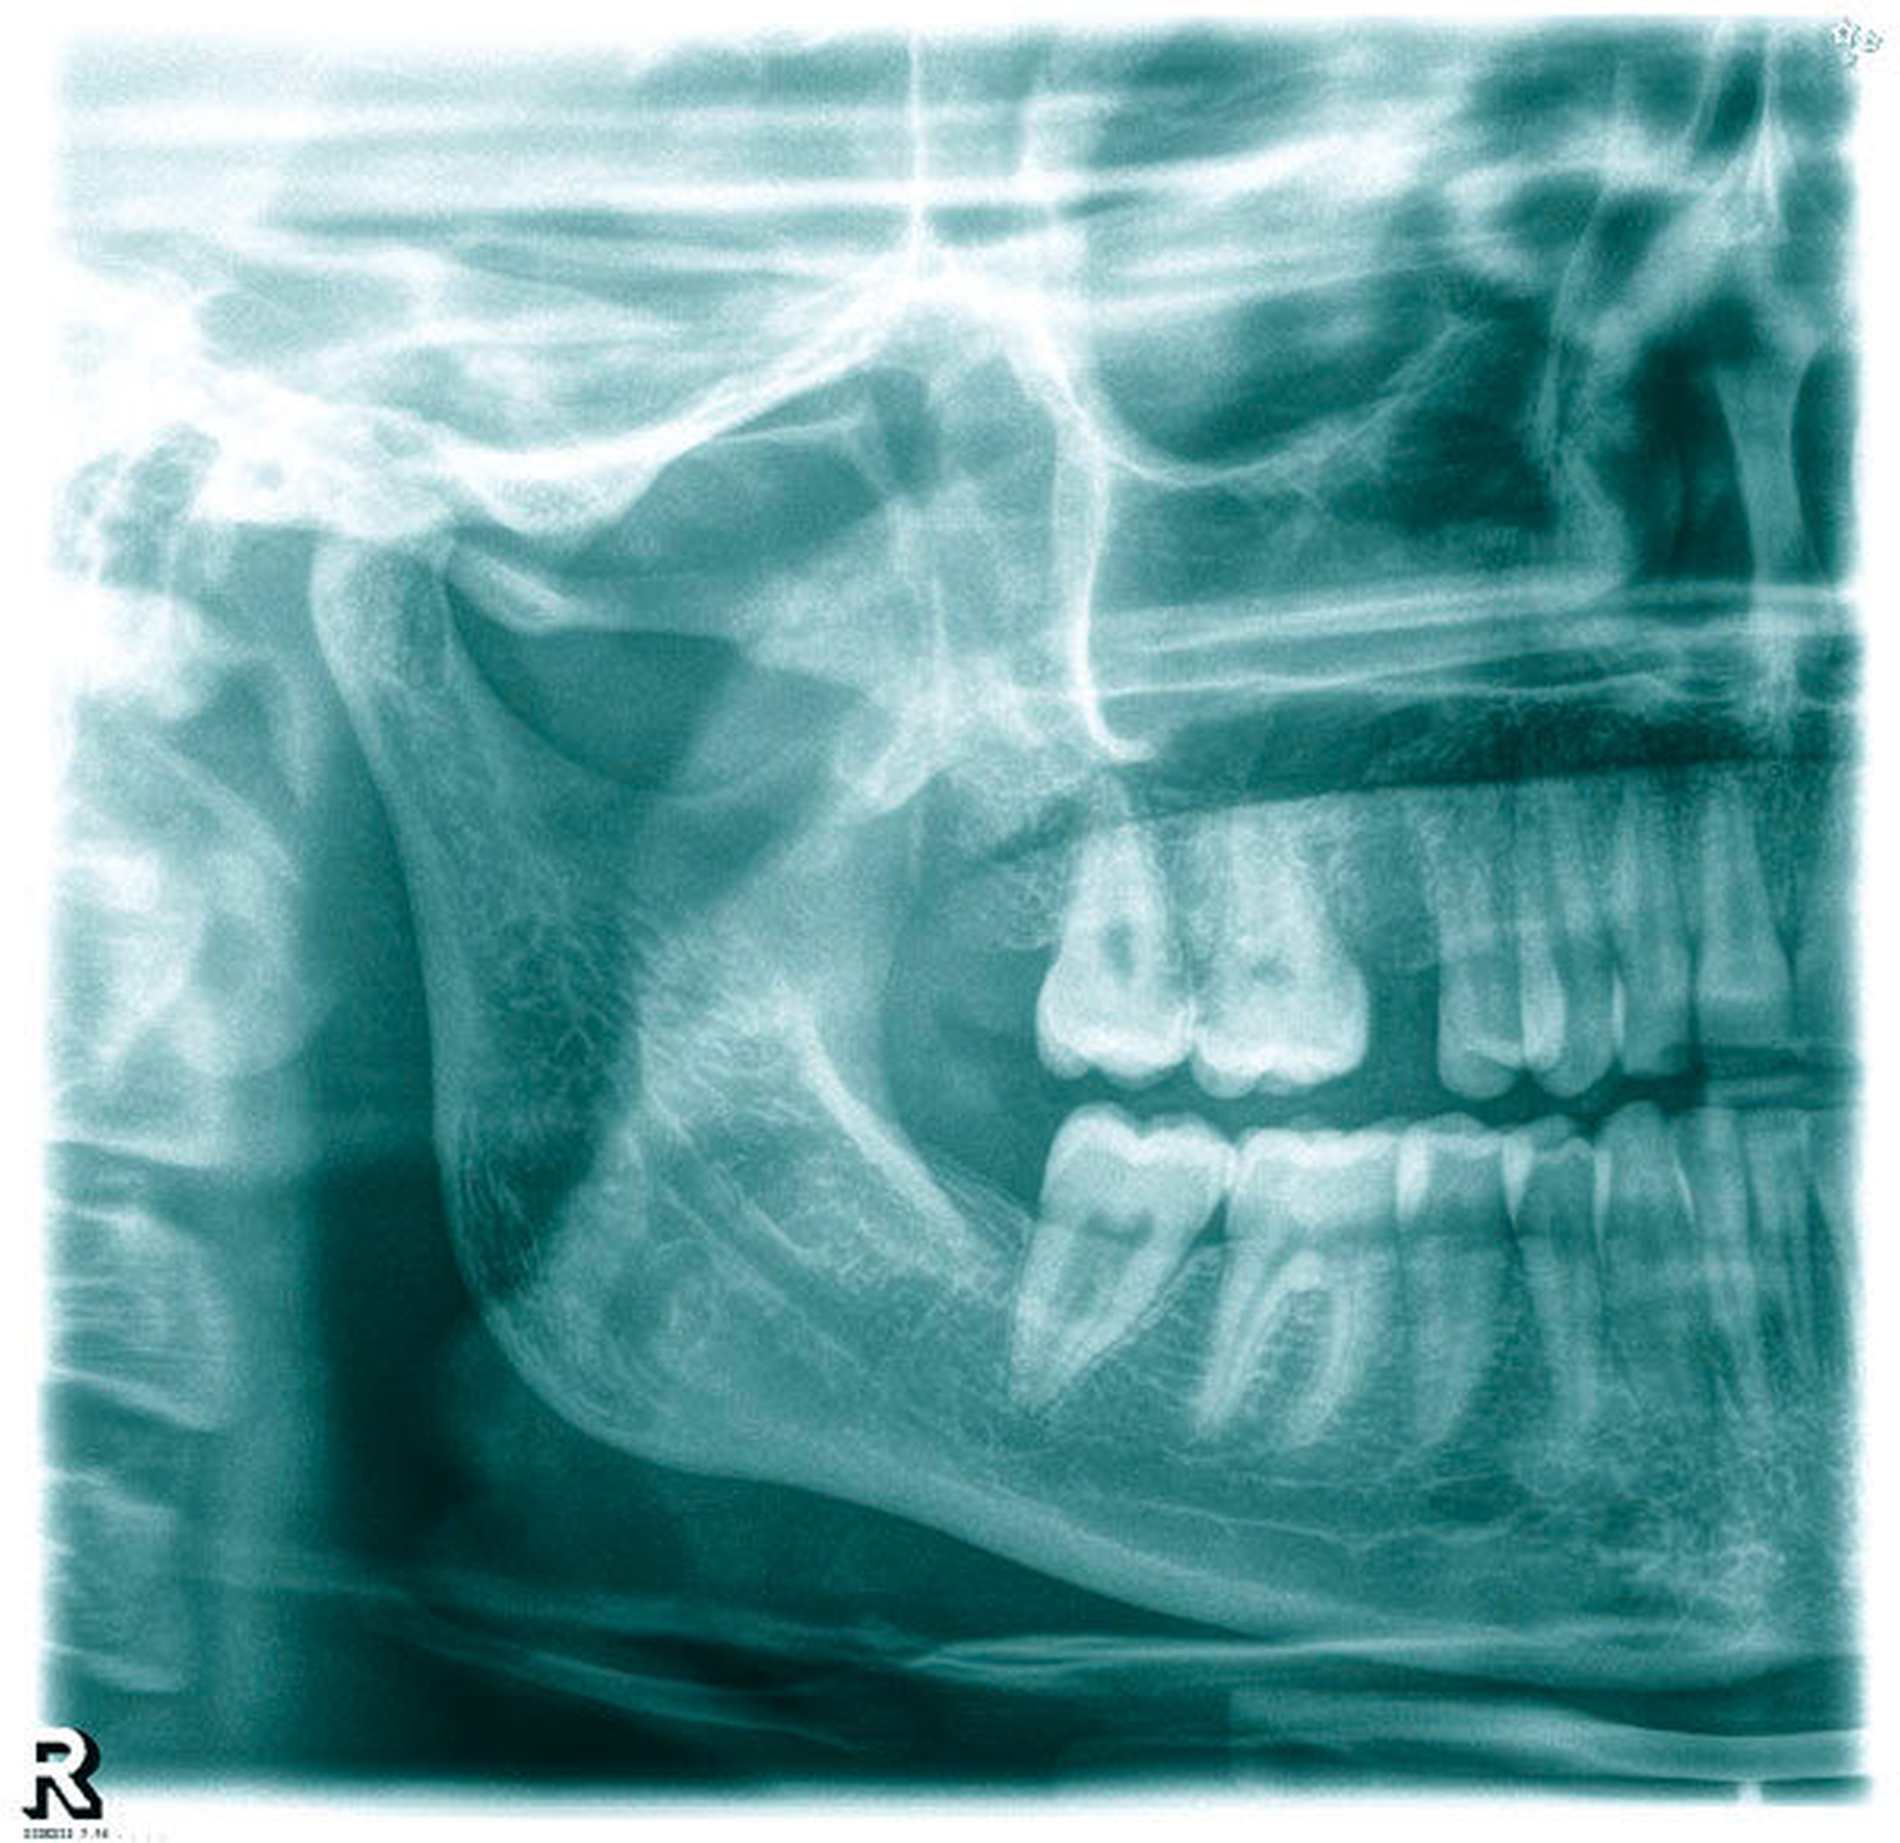

Nach Entfernung des Knochens wurde bereits der durch die Kieferhöhlenschleimhaut schimmernde Fremdkörper sichtbar (Abbildung 2), der gemeinsam mit einem Teil der deutlich verdickten Schleimhaut entfernt wurde. Bei der anschließenden Inspektion der Kieferhöhle imponierte eine Ansammlung von zystischem Granulationsgewebe, das ebenfalls entfernt und zur histopathologischen Aufbereitung eingesandt wurde (Abbildung 3). Die Kieferhöhle wurde endoskopisch nach Granulationsresten untersucht und durch Spülung gereinigt. Da das Ostium naturale weit offen war, konnte auf eine Infundibulotomie verzichtet werden. Das faziale Fenster wurde mit einer resorbierbaren Membran mit langer Standzeit verschlossen, das Periost geschlitzt, Fenster und Alveole plastisch gedeckt (Abbildung 4). Der Patientin wurden zusätzlich ein orales Antibiotikum, abschwellend wirkende Nasentropfen und Analgetika rezeptiert. Überdies wurde auf ein zweiwöchiges Schneuzverbot hingewiesen. Die histopathologische Untersuchung ergab unspezifische granulomatöse Infiltrate mit ausgedehnten Nekrosen sowie septierte Hyphen im Sinne eines Aspergilloms. Der Fremdkörper entsprach wie erwartet einem Materialrest der Wurzelfüllung. Die Patientin wurde in einen engen ambulanten Recall eingebunden. Die Nahtentfernung erfolgte nach zehn Tagen. Nach drei Monaten kam die beschwerdefreie Patientin zur Kontrolle.